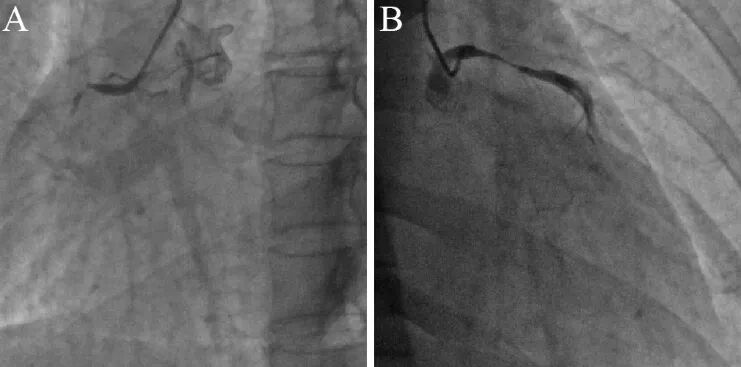

次日行冠状动脉造影提示三支临界性病变(图9)。左主干狭窄30%~40%;前降支弥漫性病变,近中段狭窄50%,第一对角支狭窄50%;回旋支开口狭窄60%,中段狭窄40%;右冠弥漫性病变,中段狭窄最重40%;后降支开口狭窄狭窄70%。造影难以判断痉挛部位,故未予支架置入。拟次日进行科内讨论药物治疗方案,并进一步评估安装起搏器或埋藏式心脏复律除颤器(ICD)的必要性和可行性。

图9 冠脉造影